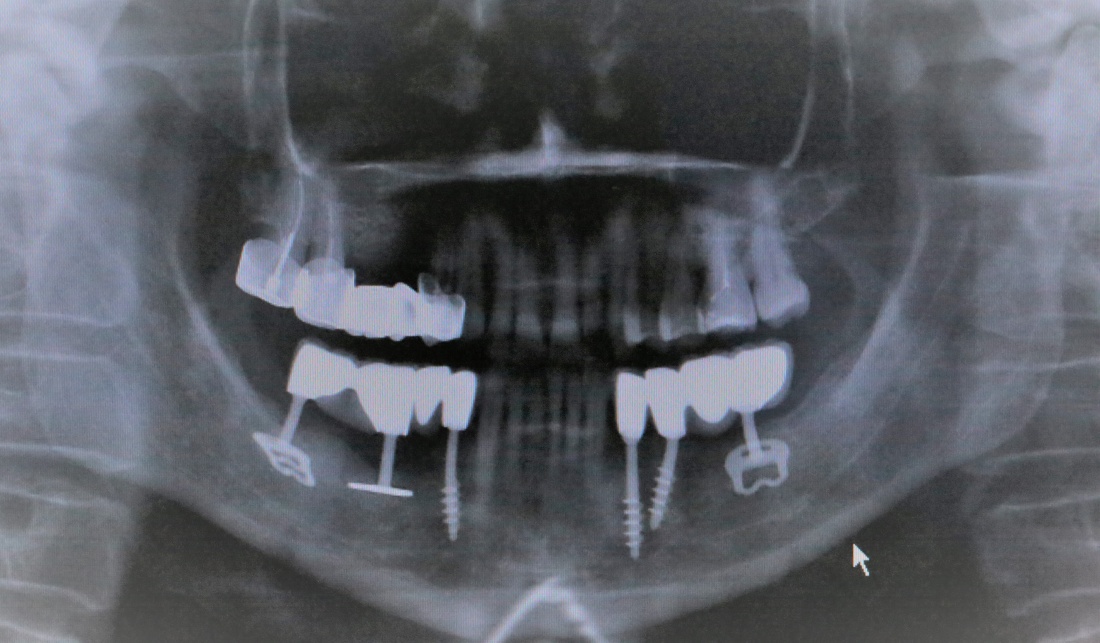

Через 4 месяца мы делаем контрольный рентгеновский снимок:

И готовимся к постоянному протезированию. Для этого мы открываем интегрированные имплантаты и устанавливаем на них формирователи десны. За пару недель они сформируют вокруг платформ имплантатов десневую манжету, которая защитит их от внутриротовой инфекции. Понятное дело, что после этого нужно откорректировать протез, что я и сделал.